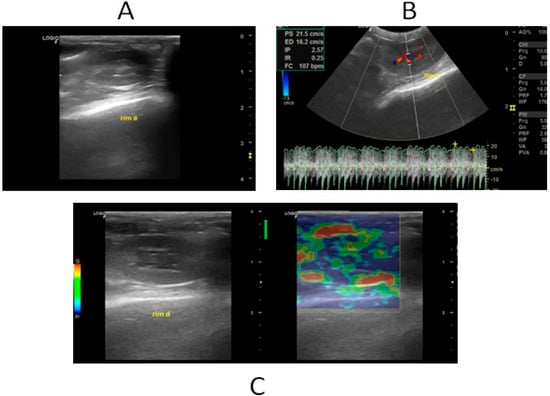

Renal ultrasonographic examinations (B-mode, Doppler, and strain elastography) (Figure 1A–C) were conducted on both groups after 24, 48, and 72 h.

Figure 1. B-mode ultrasound, Doppler, and basal renal elastography. (A) Renal B-mode ultrasound demonstrating a border with regular contours, uniform echotexture, echogenicity, and a normal corticomedullary relationship. (B) Renal Doppler evaluation demonstrating renal artery resistivity index within normal limits. (C) Renal strain elastography demonstrating variable colorimetric pattern, but with more pronounced blue areas in the cortex and green areas in the medulla, reflecting high stiffness in the cortex and low stiffness in the medulla.